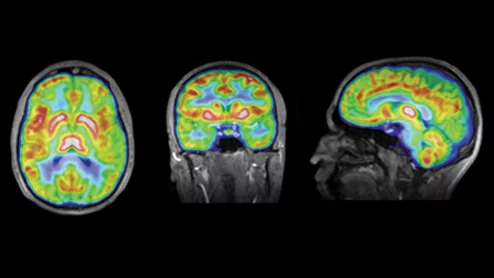

Thanks to AI, clinicians can use mammograms to do a lot more than identify signs of breast cancer. Researchers explored data from nearly 50,000 patients, presenting their findings in Heart.